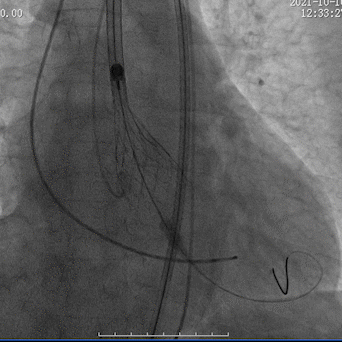

瓣膜释放至可回收极限处造影

瓣膜完全释放后造影